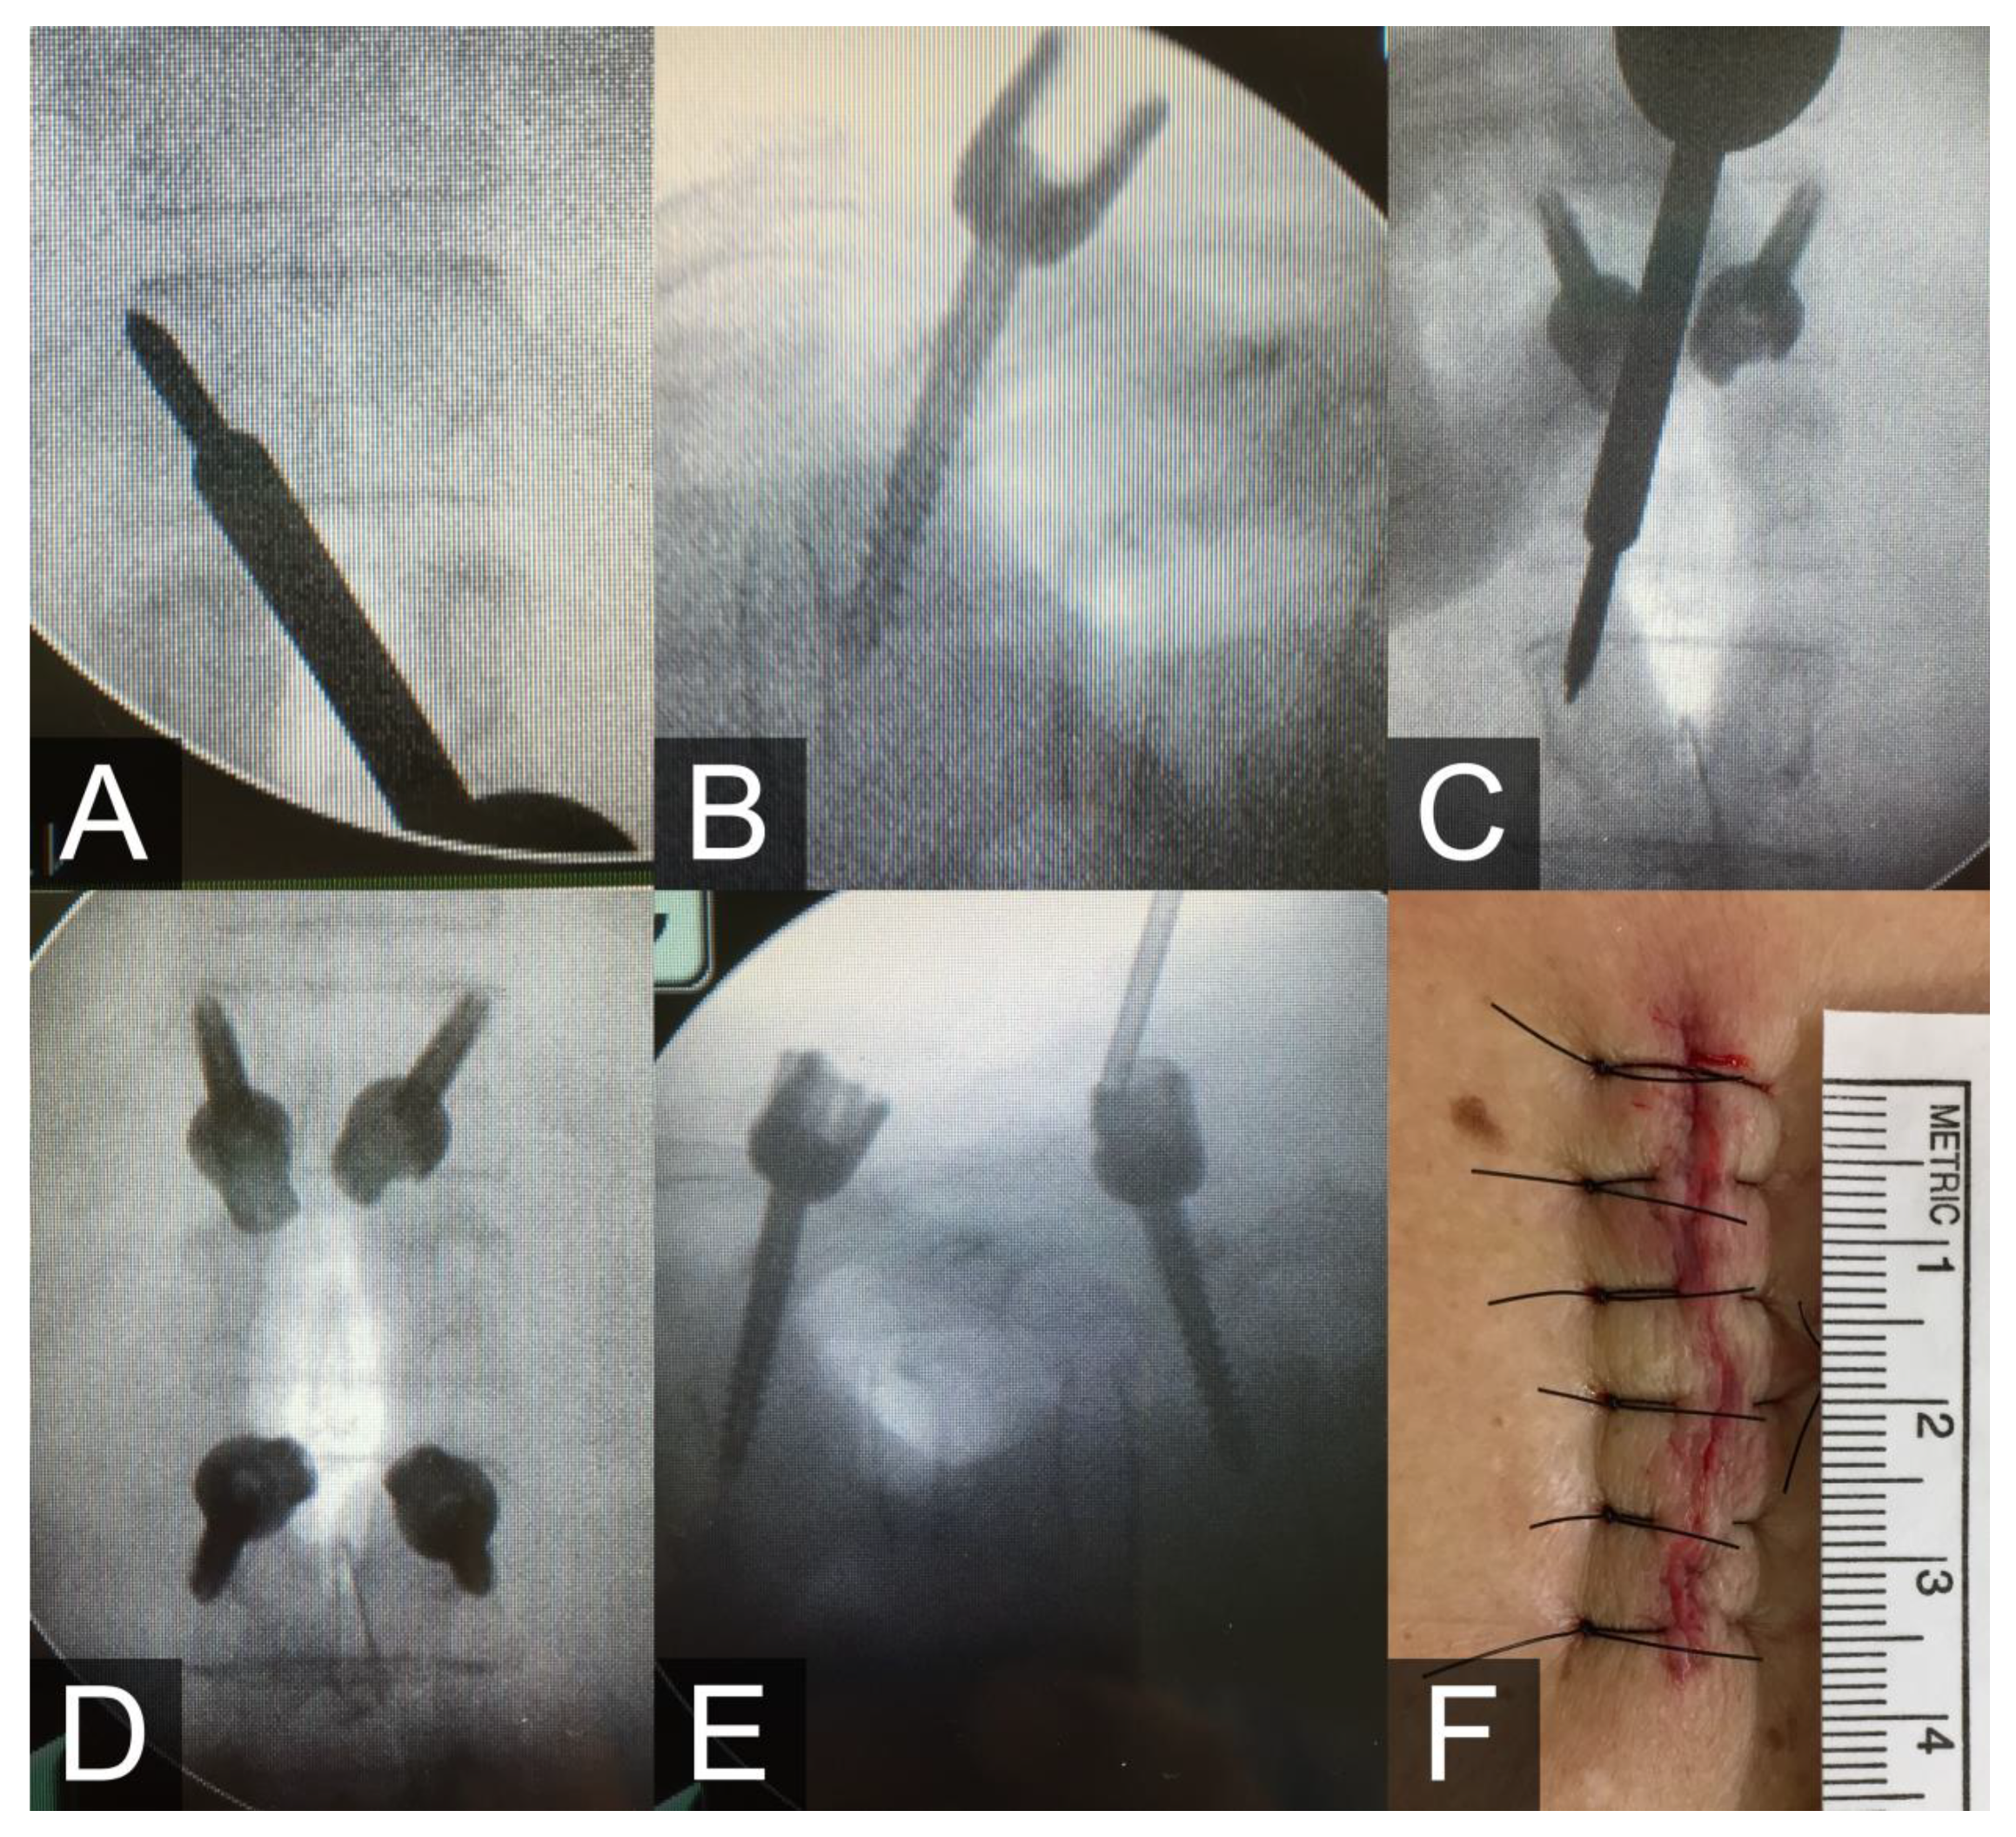

During the surgery, the patient was placed in the prone position. We drew lines at the entry points at each level under C-arm localization, and an incision was made between the T12 and L2 lines. After making a skin and fascia incision, we dissected the muscles bilaterally. Under fluoroscopic guidance in the anterior-posterior view, a pilot hole was made using the sharp tip of a cannulated awl at the T12 left pars interarticularis; the awl was positioned at approximately five o’clock, and was aimed to the eleven o’clock point of the facet joint (Figure 2A). We subsequently adjusted the angulation to make the trajectory length approximately equal to the anterior portion of the awl and slowly tapped the tract until the junction of the slender part touched the pars. We then removed the cap with the wire and inserted the cannulated screw under the guiding pin (Figure 2B). The sagittal angle was adjusted in the cephalocaudal direction at L2 to minimize the length of the incision and the need for muscle dissection (Figure 2C). After four screws were inserted (Figure 2D,E), vertebroplasty with cement was performed under fluoroscopic guidance.

Figure 2.

(A) The cannulated awl aimed from the five o’clock to the eleven o’clock point of the left pedicle of T12. (B) The inserted cannulated screws of T12. (C) The trajectory angulation was adjusted slightly in the lateral-caudal direction at L2. (D,E) The anterior-posterior view (D) and lateral view (E) after screws were inserted in the typical inferior to superior direction at T12 and in the superior to inferior direction at L2. (F) The measured wound length was 4 cm.